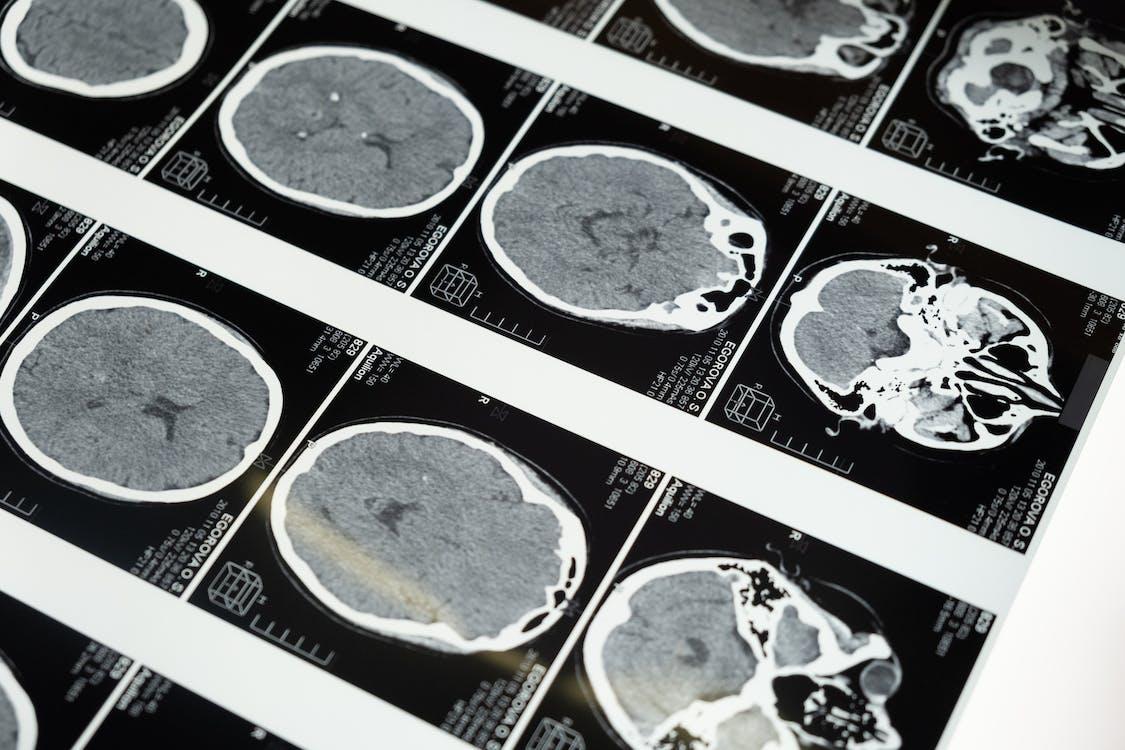

This term includes a wide range of tests that are used to create images of different parts of the body. These images play a major role when it comes to:

Some of the prominent methods encompass CT scans, X-rays, ultrasound, and MRI. Each method employs distinct technological advancements to generate visual representations. The diverse array of imaging techniques enables healthcare practitioners to gain insights into the inner workings of a patient’s anatomy. As a medical personnel, knowing how to reduce jpg size on MacMac will help you have an easy time sharing files with your patients. Knowing how to reduce jpeg file size on Mac will ensure that your Mac always has enough space to store more files.